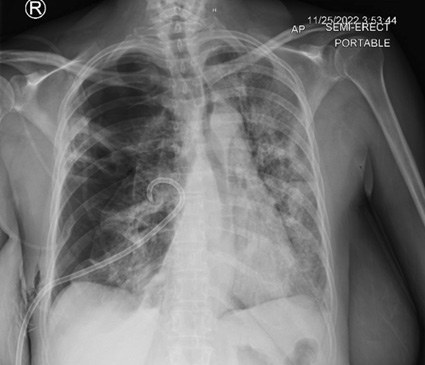

A 53year old woman with a history of alcohol use disorder, COPD, asthma and >20 pack year smoking history presented to the emergency department for two days of worsening shortness of breath and cough with rusty brown sputum and occasional streaks of blood. She denied any fever or chills but endorsed night sweats which she attributed to menopause. On initial evaluation the patient was afebrile, hemodynamically stable and saturating well on room air. Initial work up was positive only for an elevated c-reactive protein of 441. Chest x-ray showed a cavitary lesion in the right upper lobe of the lung measuring 5.7x4.3cm and bibasilar subsegmental atelectasis. Notably, the patient had a chest x-ray 6 months prior that showed no cavitary lesions. The patient was put on oxygen supplementation to assist in resolution of the atelectasis. Subsequent CT chest imaging on the same day showed a 5.1x4.3x5.7 cm thick-walled cavitating lesion in the right upper lobe with right bronchial lymphadenopathy and a small right apical pneumothorax and mild basilar effusion. The patient was put in isolation due to concerns for tuberculosis and further work up was sent including mycobacterial culture along with another infectious workup. Rheumatologic workup was also done secondary to concerns for granulamtosis with polyangitis. She was started on broad coverage with ceftriaxone, doxycycline, and metronidazole (Figures 1-3).

Figure 1: Single view chest X-ray showing thick walled cavitary leision in the right upper lobe 5.7x4.3cm; Yellow Arrows.